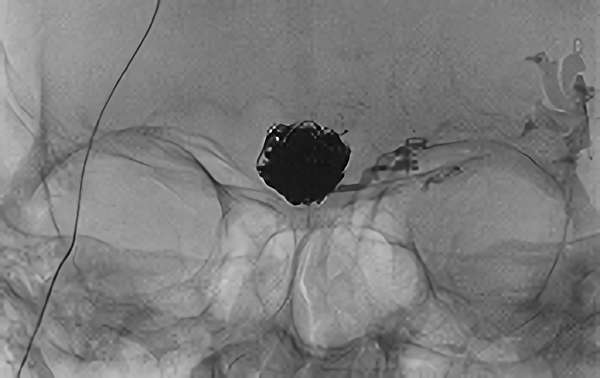

No.1617 手術前